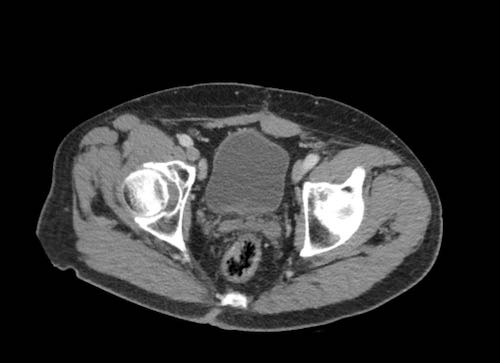

Cuộn xem ảnh CT

Ca lâm sàng 1

Cuộn qua các lát cắt.

Bạn có thể phát hiện tất cả các tổn thương cấy ghép phúc mạc không?

Bệnh nhân này đã được phẫu thuật và toàn bộ phúc mạc được ghi nhận phủ kín bởi các tổn thương u dạng kê.